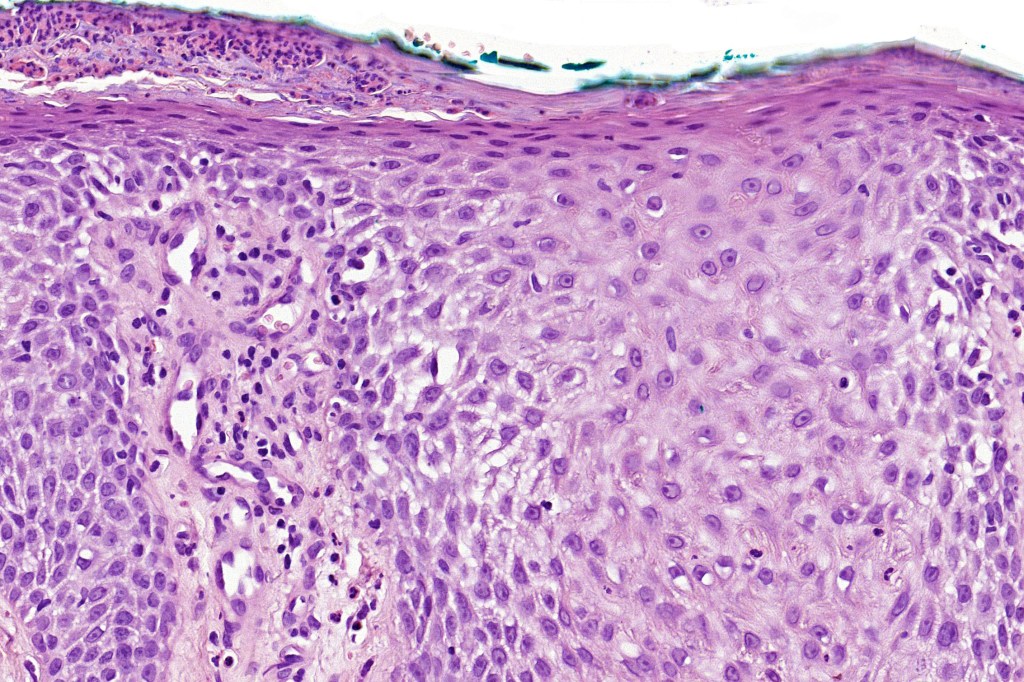

•Sharply demarcated acanthosis/psoriasiform hyperplasia; bland epithelium

•Cytoplasmic pallor or clear cell change; spongiosis sometimes present

•Characteristic intraepidermal adnexal epithelial sparing